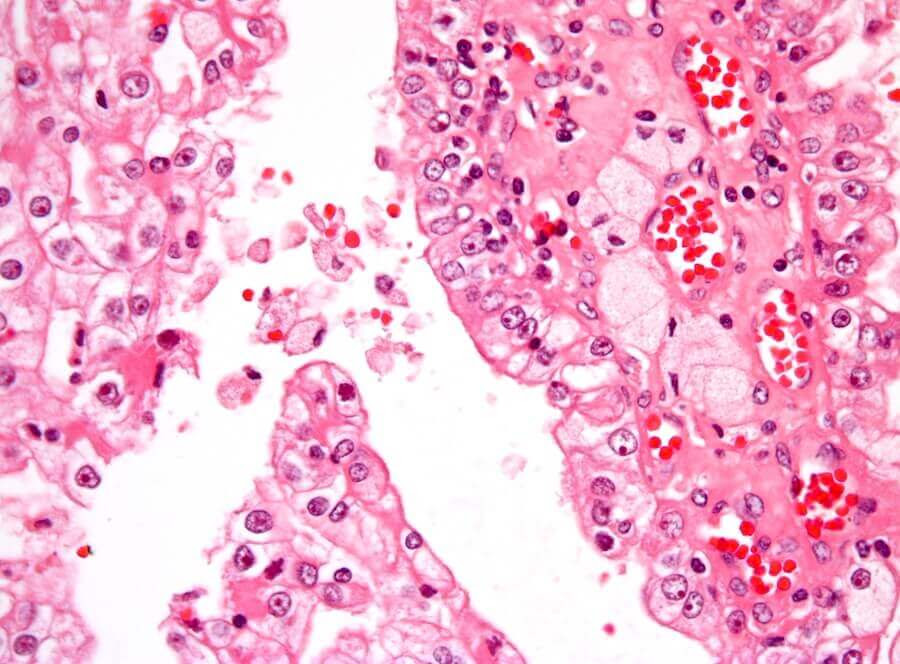

Cancer uppträder när maligna celler delar sig utan kontroll i kroppen. Den vanligaste typen av njurcancer hos barn kallas Wilms-tumör. Det är en solid tumör och bildas i den omogna njurvävnaden.